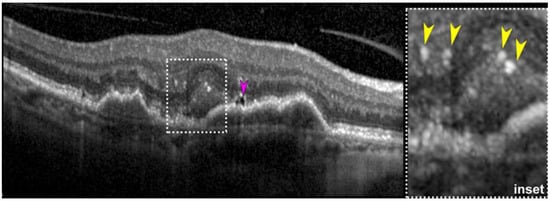

- Fernandez-Avellaneda, P.; Freund, K.B.; Wang, R.K.; He, Q.; Zhang, Q.; Fragiotta, S.; Xu, X.; Ledesma-Gil, G.; Sugiura, Y.; Breazzano, M.P.; et al. Multimodal Imaging Features and Clinical Relevance of Subretinal Lipid Globules. Am. J. Ophthalmol. 2020, 222, 112–125. [Google Scholar] [CrossRef]

- Fragiotta, S.; Parravano, M.; Costanzo, E.; De Geronimo, D.; Varano, M.; Fernandez-Avellaneda, P.; Freund, K.B. Subretinal Lipid Globules an Early Biomarker of Macular Neovascularization in Eyes with Intermediate Age-Related Macular Degeneration. Retina 2023, 43, 913–922. [Google Scholar] [CrossRef]

- Mukkamala, S.K.; Costa, R.A.; Fung, A.; Sarraf, D.; Gallego-Pinazo, R.; Freund, K.B. Optical coherence tomographic imaging of sub-retinal pigment epithelium lipid. Arch. Ophthalmol. 2012, 130, 1547–1553. [Google Scholar] [CrossRef]

- Li, M.; Dolz-Marco, R.; Messinger, J.D.; Sloan, K.R.; Ferrara, D.; Curcio, C.A.; Freund, K.B. Clinicopathologic Correlation of Aneurysmal Type 1 Neovascularization in Age-Related Macular Degeneration. Ophthalmol. Retina 2019, 3, 99–111. [Google Scholar] [CrossRef]

- Christakopoulos, C.; Pryds, A.; Larsen, M. Subretinal lamellar bodies in polypoidal choroidal vasculopathy. Acta Ophthalmol. 2013, 91, e248–e249. [Google Scholar] [CrossRef]